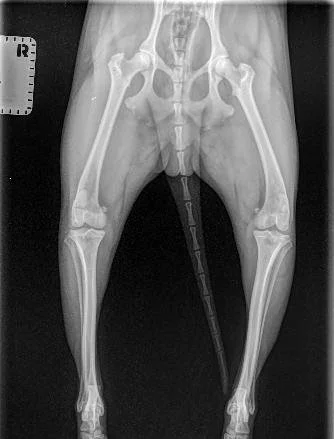

On Friday April 3rd Cosmo began limping on his left hind leg. 5 days later he was diagnosed with a Medial Luxating Patella at a grade 3 in his left knee. We have surgery scheduled for April 29th and are raising money to cover his surgery, post op recovery care, and all of our supplies we need in this next chapter.